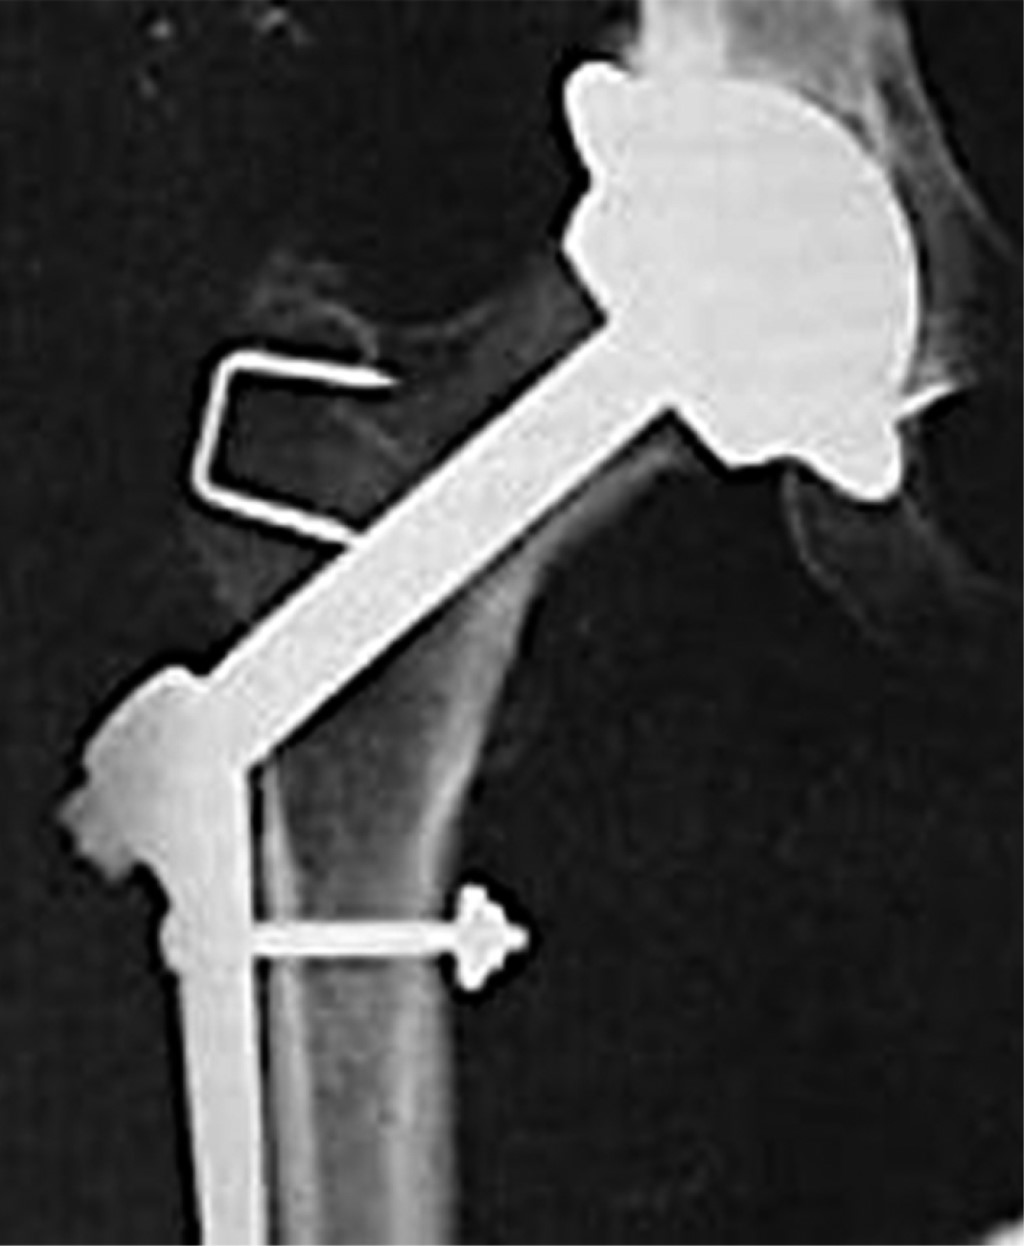

El siguiente hito ocurrió en 1943, cuando Moore y Bohlman,42 trabajando en Austenal Labs (que se convertiría más tarde en Howmedica), diseñan una prótesis que invade el espacio intramedular metadiafisiario con vástagos formales (no sólo con "espigas"), con el fin de mejorar la estabilidad del implante. Hasta antes de esta propuesta, ninguna prótesis invadía el espacio intramedular con el concepto de estos autores. La prótesis de Moore (Figura 12A) fue modificada por el mismo autor y el diseño final cuenta con perforaciones a nivel de su tercio proximal para facilitar la fijación por crecimiento óseo por invasión en esos sitios.43 Casi al mismo tiempo Fred Thompson44 e Irwing S. Leinbach45 presentan otros modelos de hemiprótesis no cementada con invasión endóstica del fémur (Figura 12B y C).

De manera simultánea a la introducción de las hemiprótesis con vástagos que invaden francamente el endostio metadiafisiario, se desarrollan las primeras prótesis "ultracortas" que tienen un vástago que sólo invade el cuello y parte de la metáfisis proximal. Los argumentos para utilizar estos diseños fue que por experiencia clínica acumulada con las copas de recubrimiento tipo Smith-Petersen, se sabía que con estas copas no se obtenía una estabilidad satisfactoria, por lo que se diseñaron estos implantes ultracortos con la esperanza de que con un vástago intraóseo cérvico-metafisario se pudiera obtener una mejor estabilidad. Así, en 1950 los hermanos Robert y Jean Judet35 proponen el diseño de prótesis con "vástagos ultracortos". Estas prótesis fueron fabricadas en un inicio con vidrio y posteriormente con el plástico acrílico (Plexiglas®) (Figura 13A y B). Poco tiempo después otros autores, incluyendo a Thompson, diseñan modelos similares fabricados con Vitalium® (Figuras 13C y 14).

Ya se ha mencionado que las prótesis de recubrimiento usadas hasta entonces no proporcionaban una estabilidad adecuada. Charles O. Townley agrega un largo y delgado vástago intramedular a las copas de recubrimiento (Figura 15A) para intentar ofrecer mayor estabilidad. Este modelo fue sustituido por el mismo autor con otros prototipos (Figura 15B y C). Aunque esta idea mejoró la estabilidad, no fue capaz de resolver el problema de aflojamiento aséptico a mediano y largo plazo.

Ya que los modelos iniciales de las prótesis con vástagos ultracortos o cortos tuvieron muy poca aceptación, la comunidad médica buscó alternativas más seguras en cuanto a estabilidad y longevidad a largo plazo. En esta búsqueda, en 1966 George Kenneth "Ken" McKee y John Watson Farrar46 presentaron un diseño de prótesis total fabricado en Vitalium® que ofrecía una alternativa diferente a las hemiprótesis hasta esa época empleadas (Figura 16). Esta idea marcó el inicio de las prótesis totales no cementadas metal-metal.

En su propuesta de diseño, McKee y Farrar incorporaban un acetábulo metálico a un vástago femoral con cuello delgado (modelo Thompson). El modelo del vástago Thompson tiene un cuello delgado que disminuye la posibilidad de colisión entre el cuello femoral óseo con el borde del acetábulo. Hay que recordar que el cuello óseo nativo debía conservarse en los vástagos cortos empleados en esa época.

En pleno auge del concepto de prótesis totales y tribología metal-metal, "Ken" McKee y Watson-Farrar hacen una serie de intentos para desarrollar una prótesis total metal-metal donde el principal problema era la estabilidad acetabular. En su último y tercer intento diseñaron un acetábulo provisto de un tornillo que roscaban en el acetábulo (Figura 17A), con lo cual se buscó resolver la inestabilidad del acetábulo diseñado por ellos años a atrás.47 Como contraparte continuaron empleando un vástago tipo Thompson no cementado. En 1970 adoptan el cemento óseo como medio de fijación, mejorando considerablemente los resultados de esta prótesis. En esa misma época (1968), Peter A. Ring47desarrolla un acetábulo muy parecido a el propuesto por McKee y Farrar (acetábulo roscado en ilíaco), pero utiliza como contraparte femoral un vástago tipo Moore, obteniendo mucho mejores resultados que los alcanzados por McKee con el vástago modelo Thompson (Figura 17B).